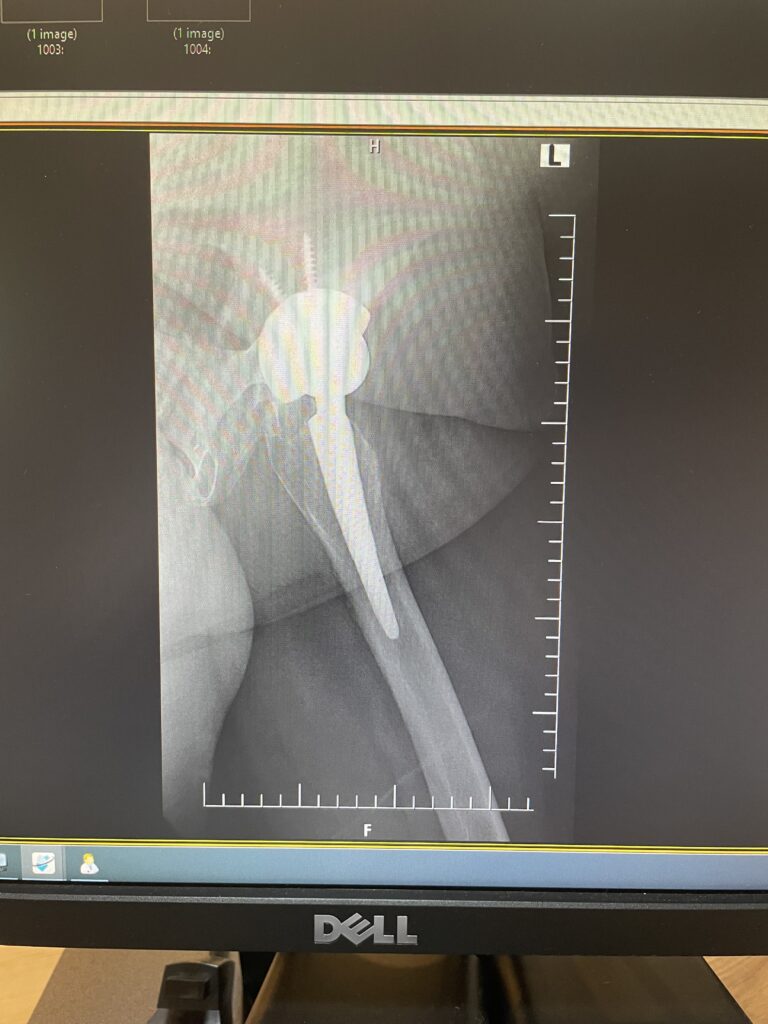

F.S.